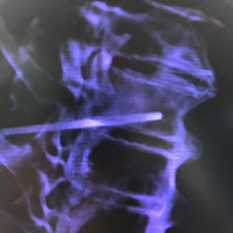

На КТ-снимке виден перелом пирамиды височной кости (указан стрелками)